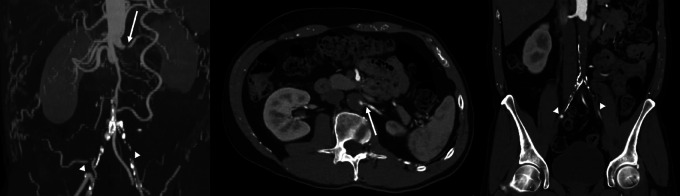

Neuroimaging in PRES: Isolated Brainstem and Spinal Cord Involvement Secondary to Aorto-Iliac Occlusive Disease-A Unique Case Report.

Teaching point: Consider atypical PRES and a vascular work-up in brainstem edema, especially in the setting of severe hypertension.